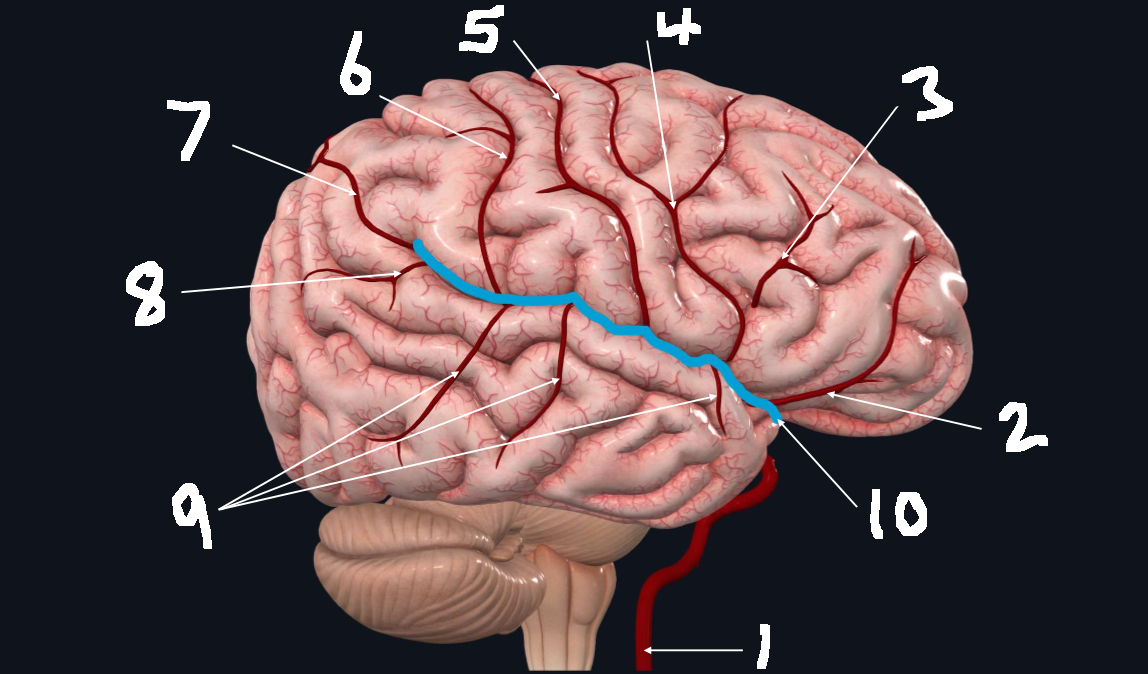

What is 1?

internal carotid artery

What is 2?

orbitofrontal artery

What is 3?

prefrontal artery

What is 4?

precentral artery

What is 5?

central artery

What is 6?

postcentral artery

What is 7?

posterior parietal artery

What is 8?

angular artery

What is 9?

temporal arteries (anterior, middle, posterior)

What is 10?

lateral cerebral fissure